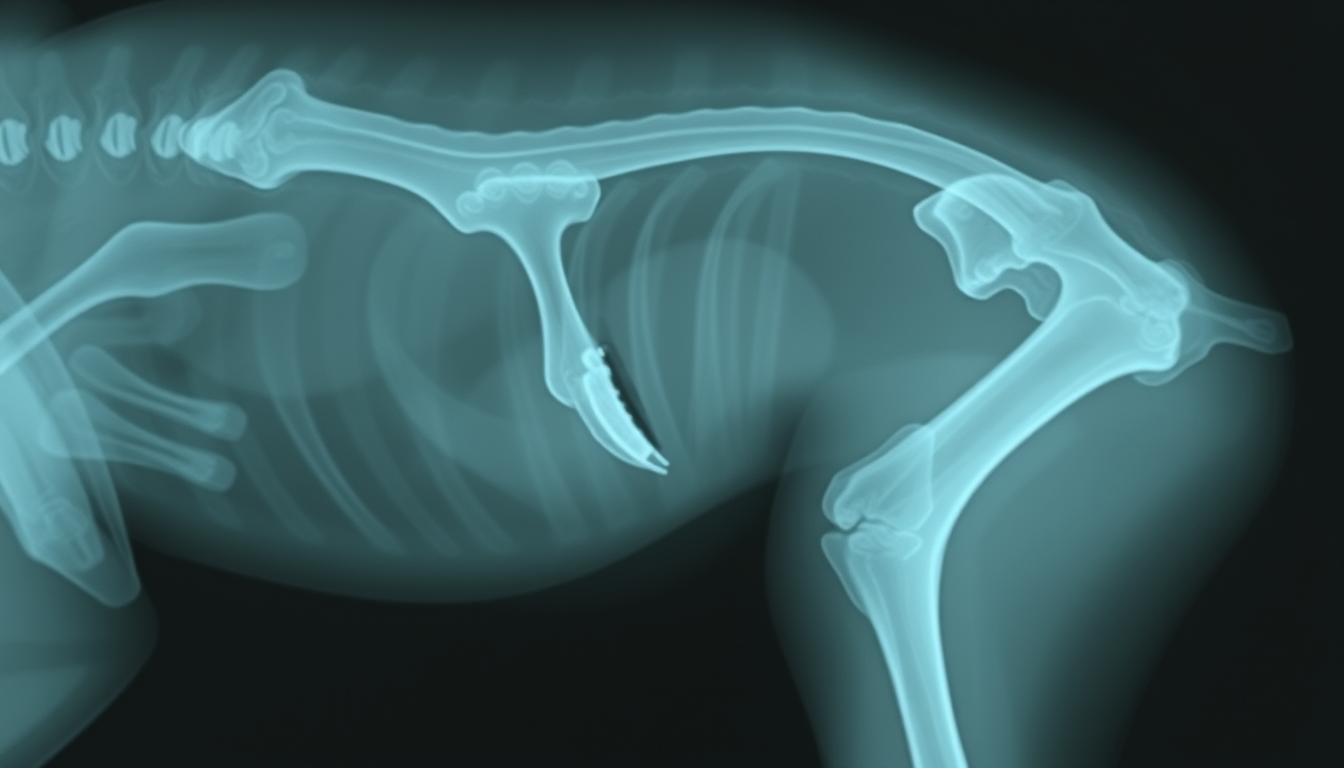

Zlom medenične kosti pri psih predstavlja resno poškodbo, ki prizadene medenični obroč. To stanje psom prinaša pomembne izzive pri mobilnosti in povzroča bolečine. Zlom se lahko razvije zaradi ekstremnih travm, kot so nesreče, padci ali neposredni udarci. Da se potrdi diagnoza, veterinarji pogosto izvajajo rentgenske preglede, ki razkrijejo natančen obseg poškodbe.

Veterinarski rentgen predstavlja osnovno orodje pri detekciji zlomov. Omogoča natančno visualizacijo kosti in okoliških tkiv, kar veterinarjem omogoča točno določitev lokacije in obsega poškodbe.